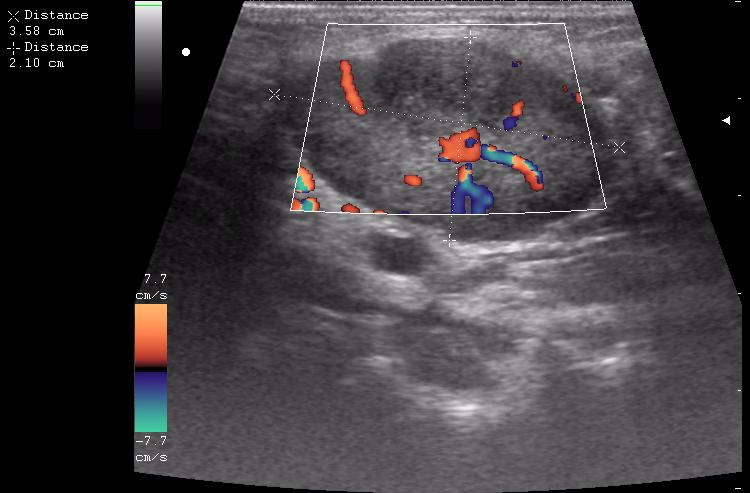

лимфоузел в правой подчелюстной области

лимфоузел в левой подчелюстной области